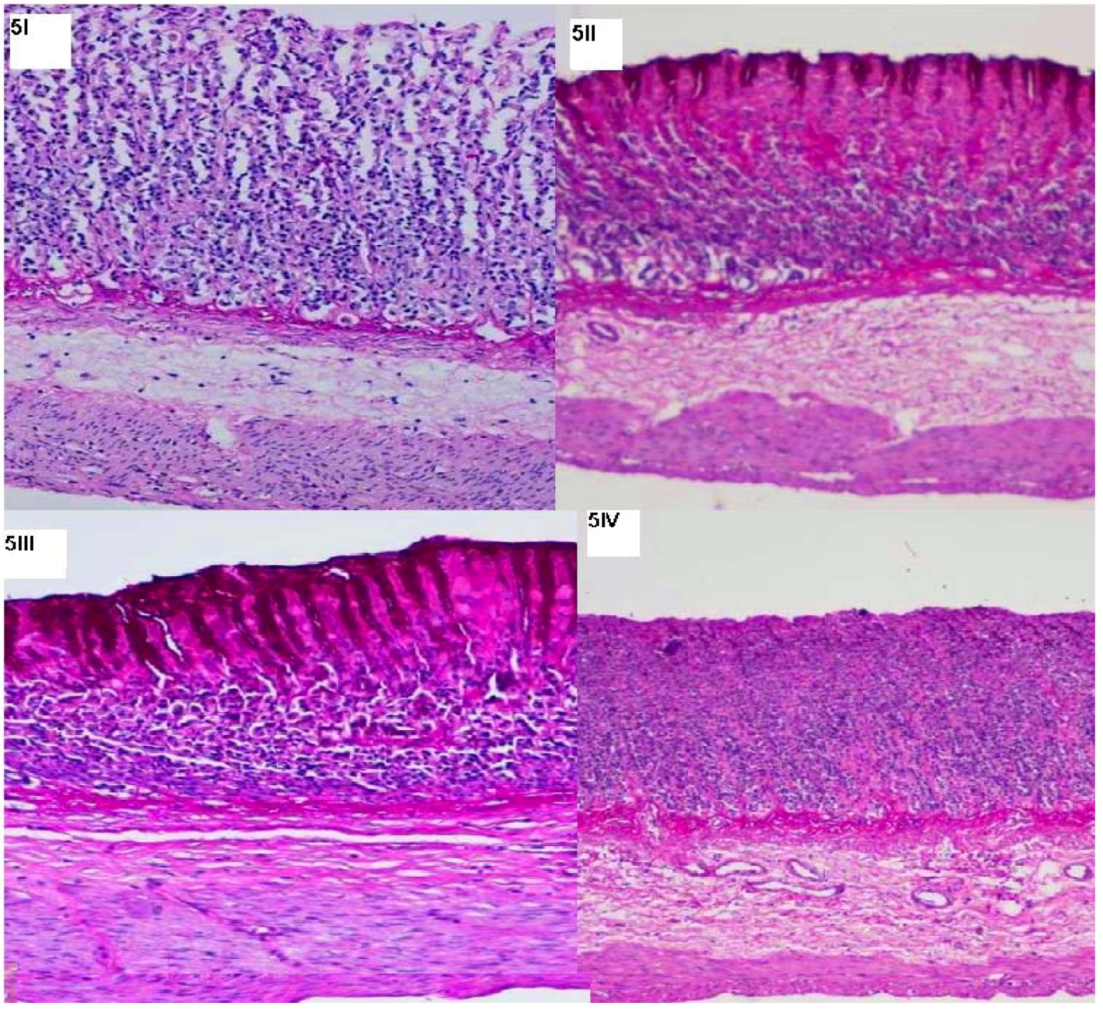

3.8. Histopathological Studies